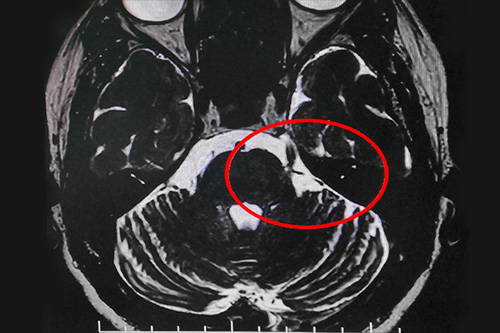

在办理入院手续后,医生详细了解了王大妈的病史资料,并为其做了三叉神经MRTA平扫+增强等相关检查。结合影像资料,沈建康教授判定王大妈的三叉神经痛系血管压迫所致,且手术指征明显,未见明显手术禁忌症。

▲患者三叉神经受压迫区域